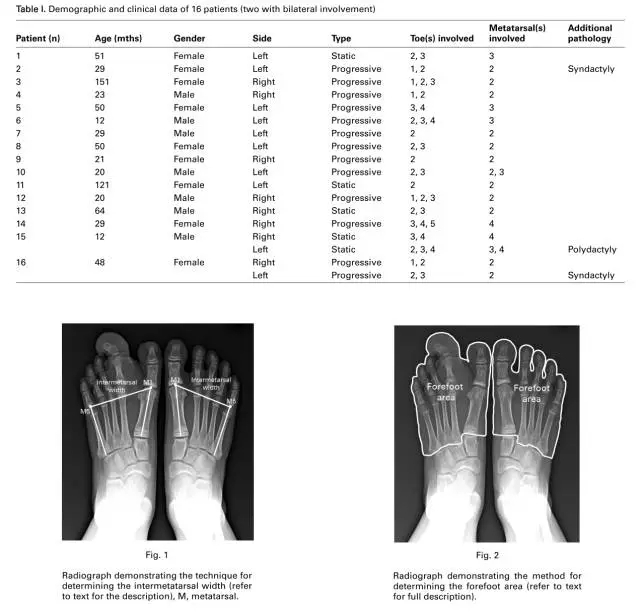

开始的时候我们让患者拍负重位的正位片其中有两名患者因为年纪太小无法站立拍片,测量跖趾关节的活动度,测量前足的宽度,跖趾关节平面,我们从第一和第五跖骨做垂直线,然后在跖趾关节处测量宽度,我们测量跖跗关节以远的足的面积大小,通过软件。同时我们测量对侧的正常足的宽度和面积,比较比率。用(OxAFQ-C评分表评价术前术后足的功能。因为患者年纪比较小,我们通过调查患儿父母来解决。在累积到相邻两个指头的患者,我们选择截除跖骨受累的,或者二者中间大的那个,尽量避免截除踇趾。然后截短和去脂在其他的跖列。当患者有三个指头受累的时候,我们截除中间的,然后截短和去脂在其他的两个。有一列患者在第二到第四巨趾,轴后型多趾我们截除了第三趾和第四跖列,保留了最外侧的趾体。

很少报道评价巨趾术后的功能。C描述了跖骨间角,第一跖列和第五跖列。在我们的研究中,我们使用了跖列间的宽度和前足的面积参数,我们相信更好的预言术后的足部的大小。巨趾是增加了长度、宽度、和高度,体积的测量会精确的反应足部的体积大小。我们没有做三维CT重建和MRI,所以我们不能测量足部的体积大小,和前足的面积,一个二维的空间测量,优于一维空间的测量,如长度和宽度。